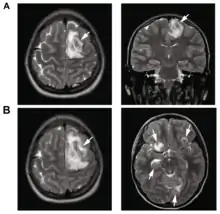

| T2-weighted MRI showing liquefied, necrotic brain tissue as a result of GAE caused by an infection of Acanthamoeba, genotype T18 | |

.png.webp)

B: T1-weighted MRI showing expansion and addition of necrotic areas 4 days later